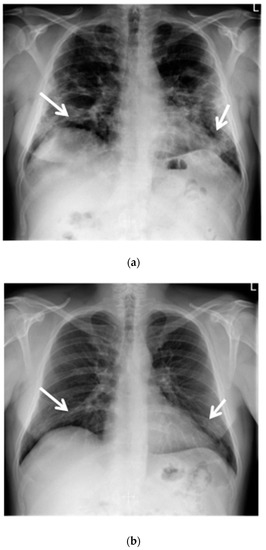

A chest X-ray revealed a reduced lung volume, and both-sided parenchymal lesions, localized in the middle and lower lung fields, predominating in the left lung (Figure 1a).

Figure 1.

(a) Chest X-ray shows opacities due to COVID-19 dominating peripherally in the lower zones of the lungs. Reduction in the volume of the lungs (white arrows); (b) Chest X-ray after six months of follow-up shows an almost complete regression of lung opacities (white arrows).

The control chest X-ray showed an almost complete regression of parenchymal lung disease, compared to the initial examination (Figure 1b). A follow-up CTPA showed complete regression of pulmonary embolism (Figure 2a,b); moreover, significant regression of parenchymal lung disease was found (Figure 3a,b).